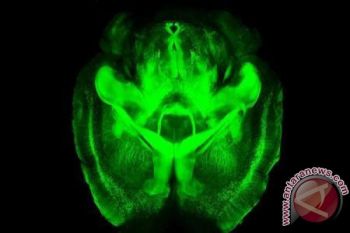

Ahli syaraf Stanford University di California, Karl Deisseroth, menemukan teknik untuk membuat otak terlihat ...